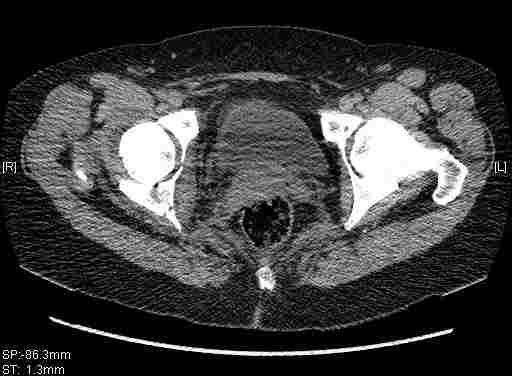

Женщина,58 лет, после ДТП 6 суток. Первично повреждение расценено как переломы ветвей лонной кости. После подтверждения повреждения вертлужной впадины,как чаще всего случается, вопрос встал о тактике. БОльшинство за консерватиное лечение.К сожалению кт у нас "во время" сломался. Прилагаю стандартные снимки вертлужки. У меня следующие вопросы к коллегам:1. Правильно ли рассценивать это повреждение как Т-образный перелом вертлужнй впадины?2. Можно ли добиться анатомической репозиции поверхности вертлужной впадины скелетным вытяжением в данном случае, если нет, что будет этому препятствовать?3. Если смещение останется таким как сейчас, через какое время появится необходимость эндопротезирования (по вашему опыту)?Спасибо.

Удалось сегодня вывести пациентку в соседнюю больницу, где есть кт. Срезы сделаны только горизонтальные.

|

Следом 3d

Приветствую,Антон.Рункова рядом нет,но после полученных данных КТ,обсуждали совместно.Итог обсуждения-развернутый ответ дать не получится,т.к.срезы выбраны не информативные.Если ориентироваться на данные 3D,то ,ИМХО,можно лечить на вытяжении.